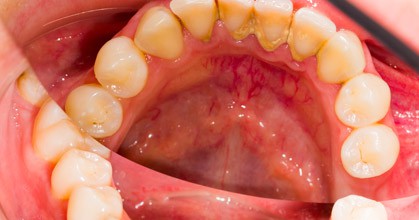

Periodontal disease (also known as gum disease and periodontitis) is a common inflammatory condition which affects the supporting and surrounding soft tissues of the tooth eventually the jawbone itself when in its most advanced stages.

Once this bacterial infection colonizes in the swollen gums pockets between the teeth starts to form, and it becomes much more difficult to remove and treat. Periodontal disease is a progressive condition that eventually leads to the destruction of the connective tissue and jawbone. If left untreated, it can lead to shifting teeth, loose teeth and eventually tooth loss.

When left untreated, gingivitis (mild gum inflammation) can spread to below the gum line. When the toxins contained in plaque irritate the gums, a chronic inflammatory response causes the body to break down and destroy its own bone and soft tissue. There may be little or no symptoms as periodontal disease causes the teeth to separate from the infected gum tissue. Deepening pockets between the gums and teeth are generally indicative that soft tissue and bone is being destroyed by periodontal disease.